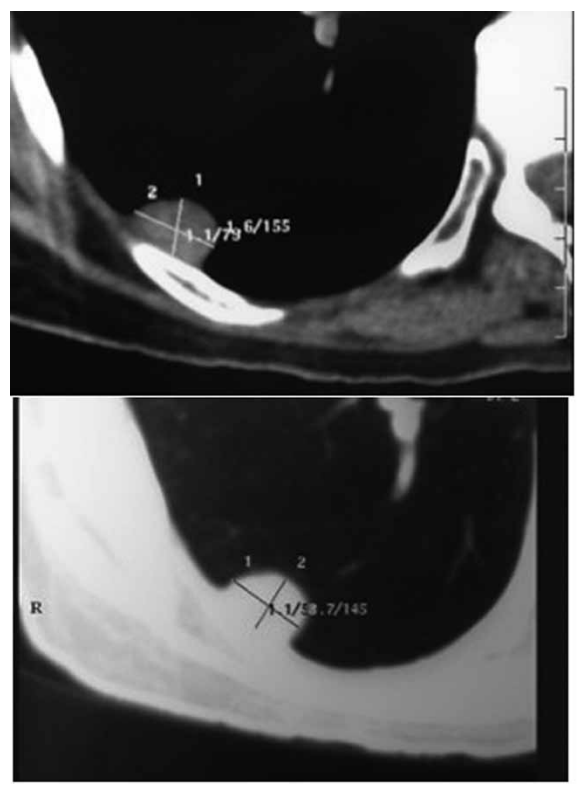

Paciente 46 anos, com tosse persistente pós-Covid-19.

Relatou um episódio de desmaio há 20 dias, atribuído à

hipoglicemia na época. Procura serviço médico, e é submetido à tomografia de tórax, conforme demonstrado a seguir:

(Arquivo pessoal; imagens usadas com autorização)

Biópsia transparietal:

Hematoxilina/eosina: tecido conectivo e células fibroblásticas.

Imuno-histoquímica: negativo para citoqueratina e antígeno carcino-embriônico. Positivo para vimentina, CD34 e para oncoproteina bcl-2.

O diagnóstico e a conduta são, respectivamente: